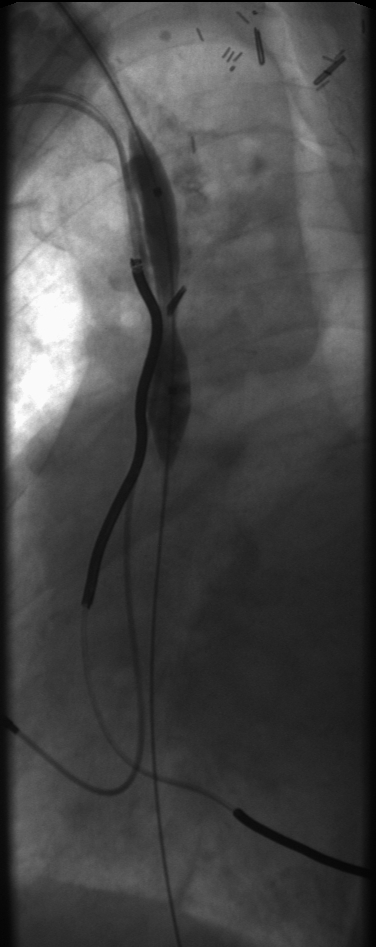

Mid-phase balloon inflation of the RBCV and SVC: Incomplete dilation of the central veins.